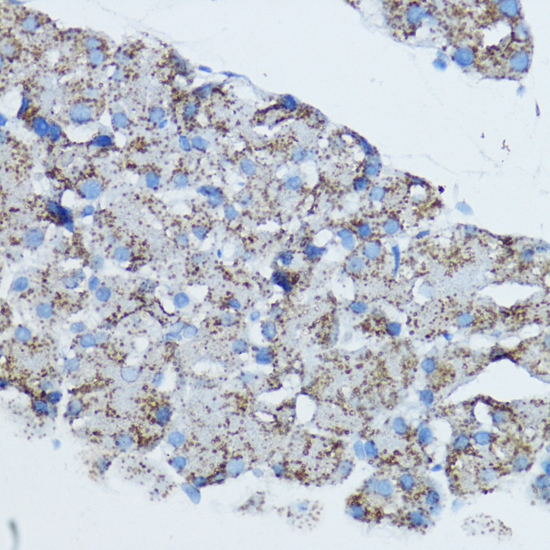

Immunohistochemistry of paraffin-embedded human placenta using Aromatase at dilution of 1:100 (40x lens).

,